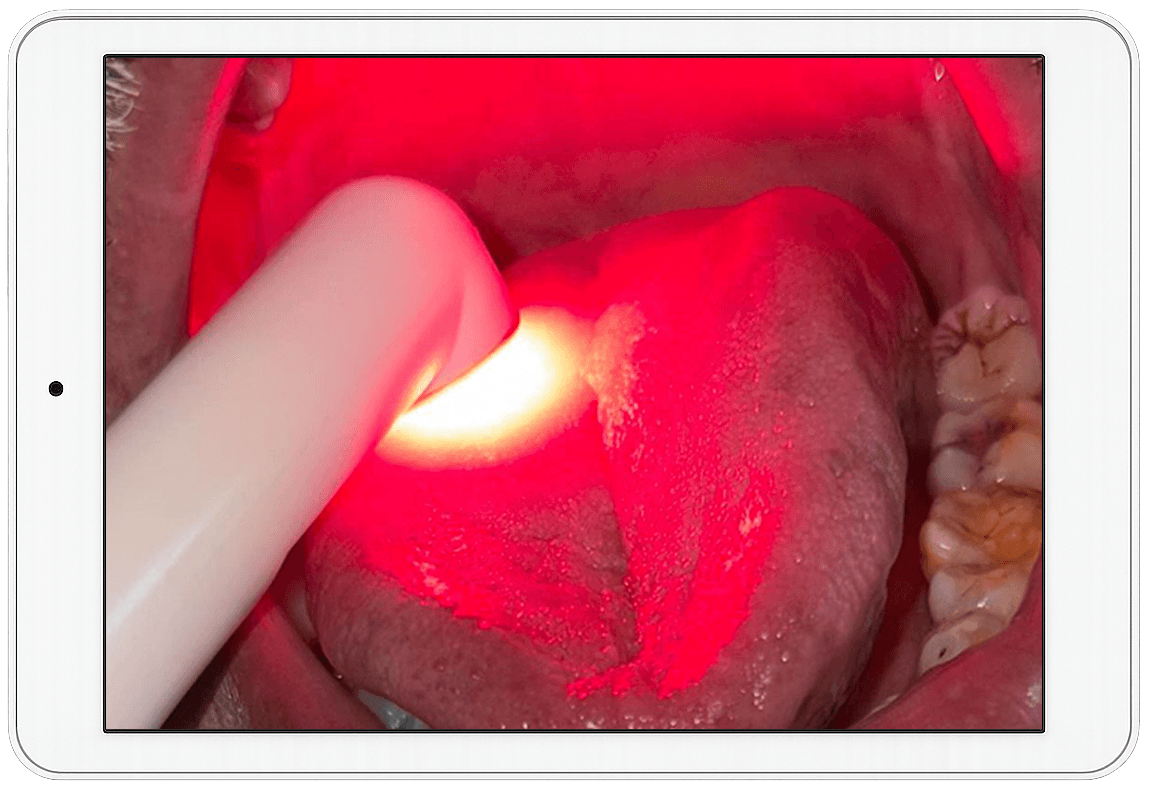

The LaserPRO App by the Asian Academy of Laser Therapy is a simple, intuitive platform designed to help Dental Professionals Master the use of Laser-assisted Treatments.

From a ‘Real’ Patient Video Repository to Weekly ‘Live’ Expert Sessions, as well as an Independent Laser Safety Officer’s (LSO) Certification (European Standards EN 60825-1, EN 207 & EN 61040), LaserPRO supports every step of your Laser Practice. It is ideal for enhancing precision, esthetics, and patient outcomes.